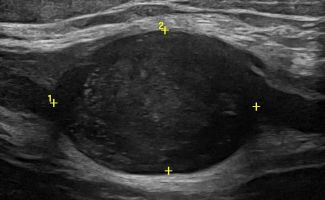

- Entrapment Syndromes (carpal tunnel syndrome, cubital tunnel syndrome, tarsal tunnel syndrome, meralgia paresthetica)

- Focal Lesions (tumors, neuromas)